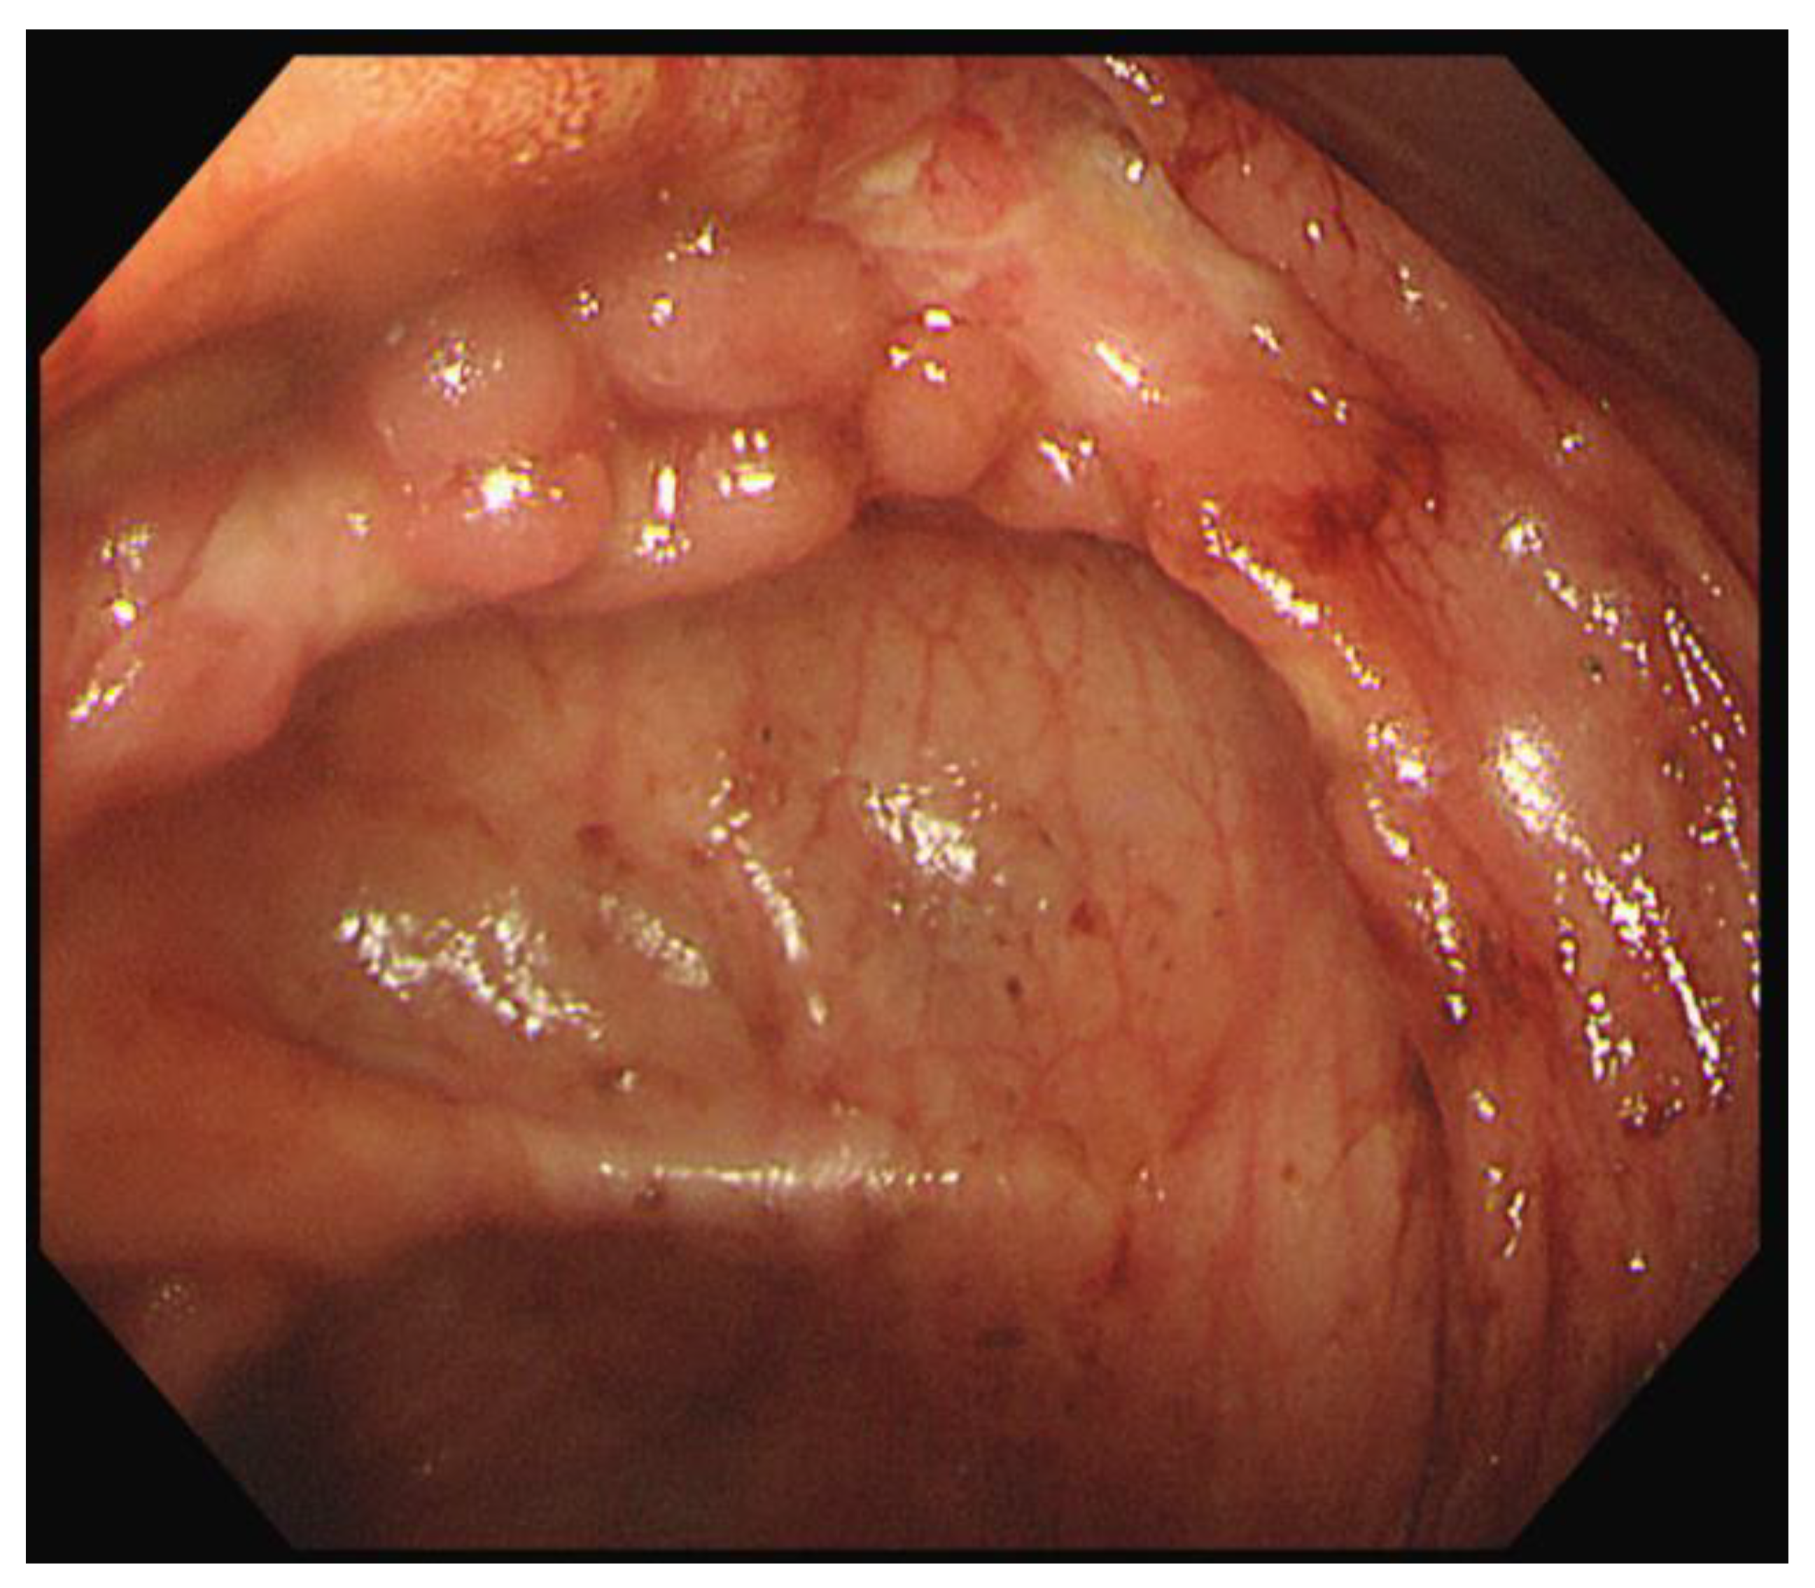

Capsule endoscopy was performed to evaluate mucosal lesions in the small intestine. Three or more ulcerations were confirmed, and fresh blood due to active bleeding was observed in the distal small intestine (Figure 5).

Figure 5.

Capsule endoscopy revealed three or more ulcers of various sizes (a) and active bleeding in the distal ileum (b).